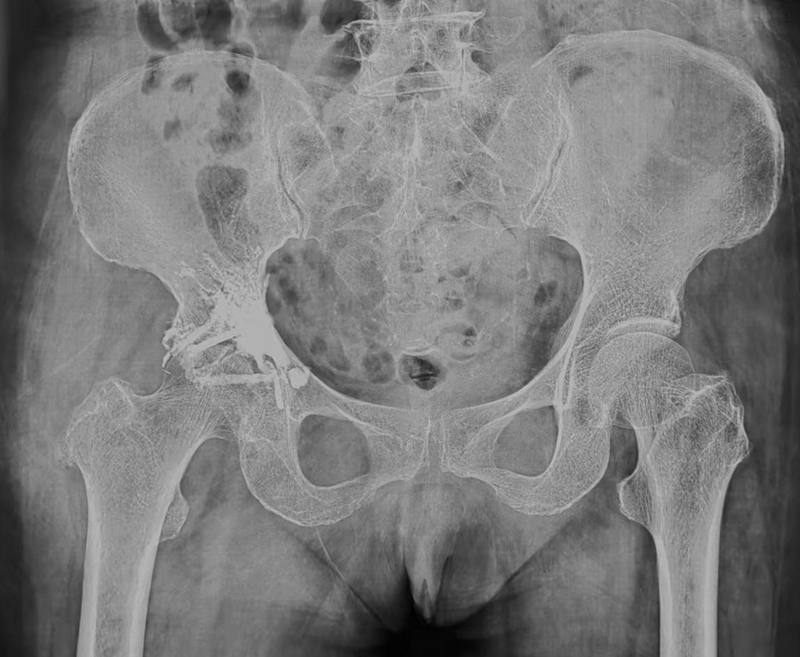

女性,68岁。因右髋部疼痛1年余,加重3月入院。患者于2018年因直肠癌行肿瘤切除术,术后系统化疗和靶向治疗,2021年发现右髋臼转移并行放疗,3月前右髋部疼痛加重,疼痛难忍,无法行走,卧床需专人陪护。

入院后经过系统检查,术前评估后建议手术治疗,经与患者及家属沟通后,采取了髋臼转移病灶射频消融骨水泥填充的姑息性手术,术后右下肢疼痛症状迅速缓解,患者由于长期卧床加疼痛,下肢肌肉萎缩、无力,经过康复锻炼能够扶拐行走,已顺利出院。但该患者由于没有彻底切除转移病灶,只是姑息性手术缓解了疼痛,如果术后其它治疗手段不及时可能很快复发。

图2a 女,68岁,直肠癌术后系统化疗和靶向治疗近5年。MR显示T1WI示右侧髋臼见片状模糊低信号骨破坏,T2WI压脂病变呈较明显高信号,外侧骨皮质破坏、毛糙,见细小垂直状骨膜增生,考虑直肠癌髋臼转移

图2b 右侧髋臼转移病灶射频消融骨水泥填充术后X片